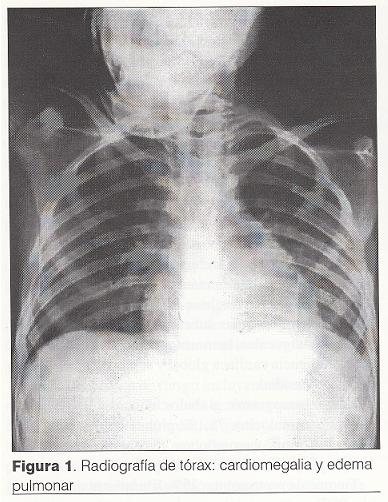

Ecocardiograma Doppler: vegetación de 9 mm de diámetro mayor a nivel de la valva mitral anterior del lado auricular. Insuficiencia mitral leve a moderada. Función contráctil de VI normal. Leve derrame pericárdico (figura 2).

Los hemocultivos obtenidos previos al inicio del tratamiento antibiótico desarrollaron colonias de EBHGA, siendo éste un criterio mayor para el diagnóstico de EI, así como la evidencia ecocardiográfica de una vegetación de 9 mm a nivel de la superficie auricular de la válvula mitral con lo que se establece el diagnóstico de EI aguda definitiva según los criterios de Duke (4).